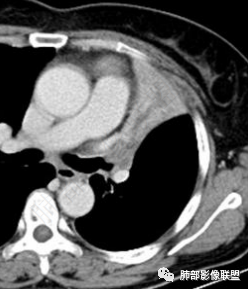

4、病例结果

1、简要病史:老年女性,以受凉后咳嗽伴胸闷就诊,无咳痰、发热及其他不适,病程4月;既往体健。实验室检查中性粒细胞稍高,PCT稍高,CEA、细胞角蛋白19片段、鳞状细胞癌抗原正常。